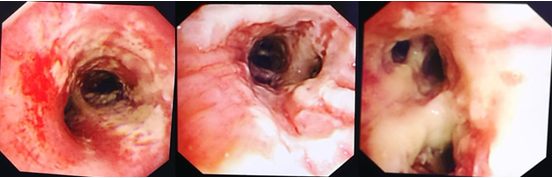

IAA患者气管镜下典型表现是气道黏膜明显充血水肿,气道黏膜表面白色假膜附着,气道狭窄及痉挛比较明显。

图片

气管镜检查的重要意义在于:①观察气道病变特点和范围;②有助于获取高质量的下呼吸道标本,提高真菌培养阳性率;③获得BALF,以辅助早期诊断(BALF GM试验等);④由于IAA患者气道黏膜病变严重,气道明显狭窄,所以患者大多存在严重的痰液引流不畅问题,通过气管镜下吸痰,可以加强痰液引流,能够在一定程度上改善患者预后;⑤可以通过气管镜进行气道内给药。

来自欧洲7个国家、美国和台湾的29名专家就IAA的诊断标准发布了专家共识,并于2020年发表在Intensive Care Medicine杂志上,他们将IAA明确分为两型,即曲霉菌性气管支气管炎和侵袭性肺曲霉菌病,这一标准也高度强调了气管镜的重要性。无论是气管镜镜下的表现,还是气管镜获取的BALF标本进行GM试验或曲霉培养,均是诊断标准中非常重要的条目。